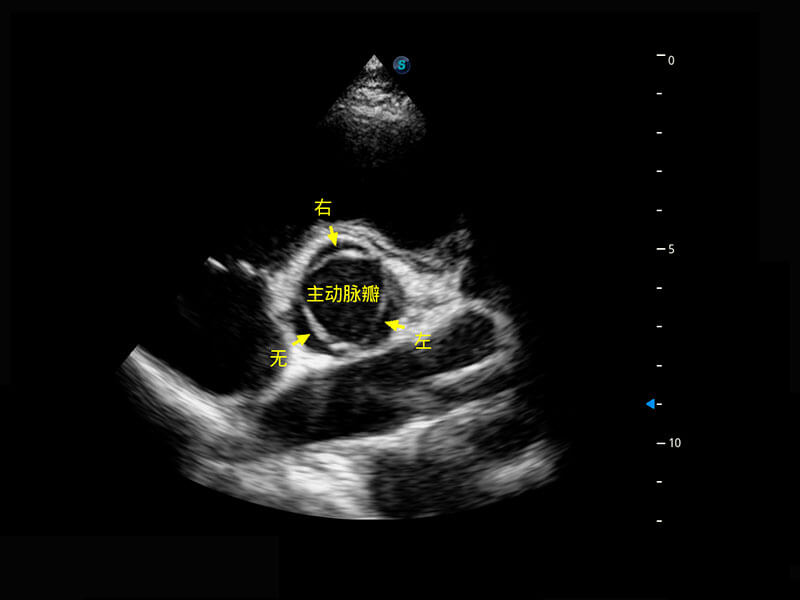

P60搭载一系列胎儿心脏成像技术,实现精细的胎儿心脏评估。

胎心容积成像